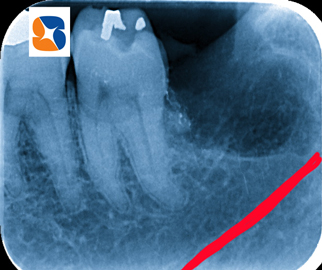

無事、歯の摘出に成功!

コラム「無事、歯の摘出に成功!」の画像